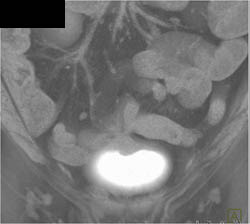

Pseudomembranous Colitis (PMC)